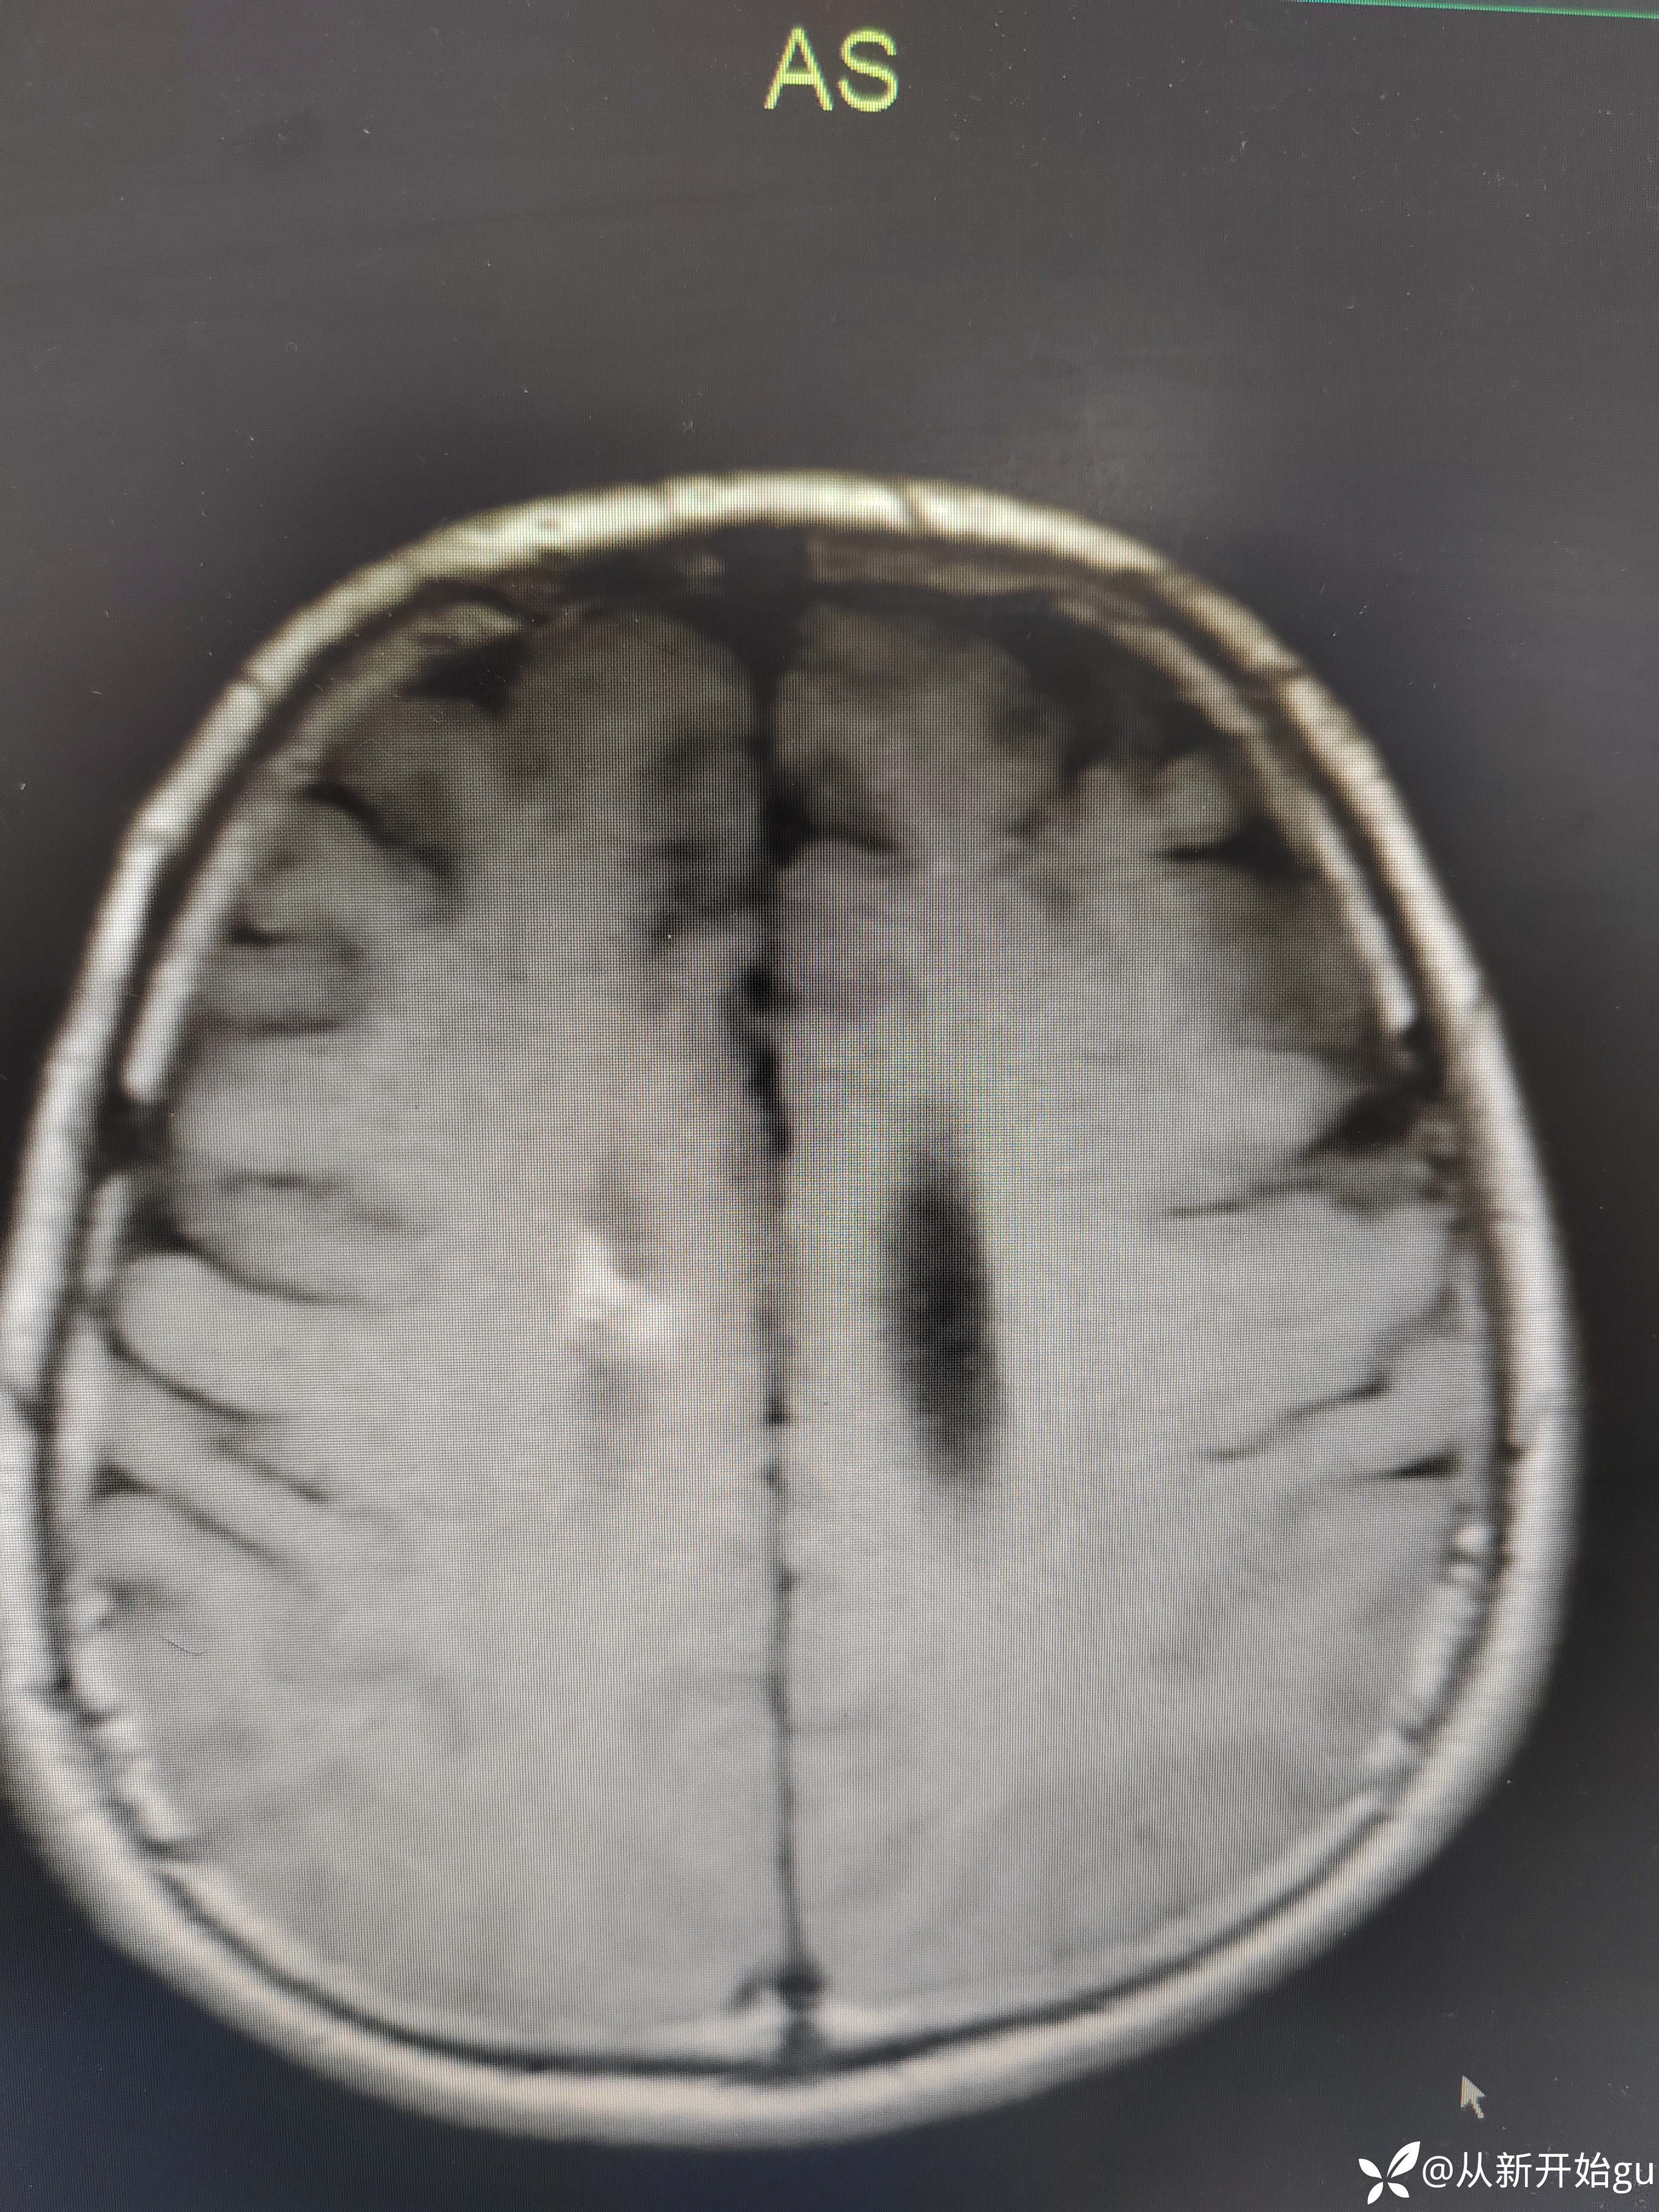

T1

T1